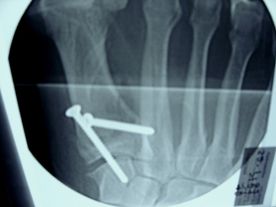

Links: Bruch der Basis des 1. MIttelfußknochens und Ruptur der Bandverbindung zwischen dem 1. Mittelfußknochen und der Fußwurzel und dem 2. Mittelfußknochen (Lisfranc).

Rechts: Rekonstruktion und Verschraubung